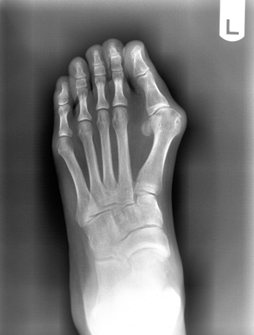

Hallux Abducto Valgus (Bunion Deformity)

Hallux valgus is one of the most recognizable deformities of the foot. (See Figures 3-7.) Investigators consistently have reported that this disorder is more common in females than males; however, this finding may be inaccurate, since the studies cited were based on relatively small numbers of subjects.22 Women are more likely than men to consult with their primary care physicians. The true prevalence of hallux valgus in the general population remains unknown. Many factors, including foot type, biomechanical instability, shoe gear, and other hereditary factors, affect the development of this deformity. Women generally have more issues with foot gear, thus giving the appearance that symptomatic hallux valgus deformity occurs more in women. 23

Figure 3. Clinical Photograph of a Bunion

Figure 4. X-Ray of a Bunion

Hallux valgus is a progressive subluxation of the first metatarsal phalangeal joint. The normal anatomic variant is slight lateral deviation in the great toe with a hallux valgus angle of less than 15 degrees. Mild deformities exhibit an angle of 20 degrees, with moderate deformities at 30 degrees and severe deformities more than 40 degrees. As the hallux moves laterally, retrograde force is placed proximally on the first metatarsal head. The medial and dorsal medial aspect of the first metatarsal becomes “prominent,” thus leading to the bunion formation. Over time, uneven degeneration of the first metatarsal phalangeal joint can lead to arthritis. It is important for the clinician to be able to differentiate the etiology of patient’s symptoms.

The presenting symptoms include pain in the medial aspect of the metatarsal phalangeal joint, with redness and swelling at the area of excessive shoe pressure. There may or may not be pain with range of motion of the metatarsal phalangeal joint. The range of motion can be mildly decreased.